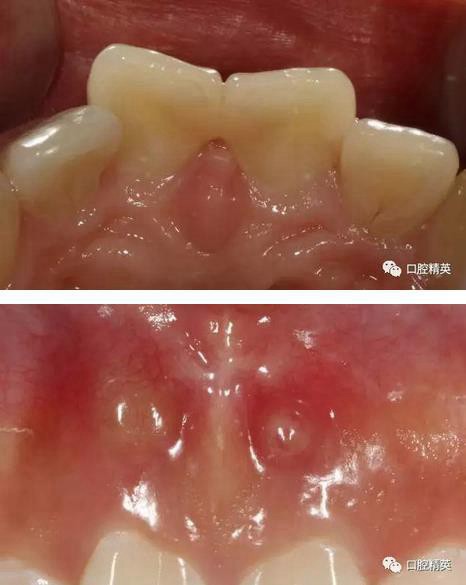

可見兩側(cè)齦緣外形不平整

激光休整牙齦前后

術(shù)前,術(shù)中,術(shù)后對(duì)比

對(duì)比來看基本達(dá)到患者預(yù)期

有一點(diǎn)不足之處在于齦緣的高低不完全一致,補(bǔ)救辦法同上——激光輕掃